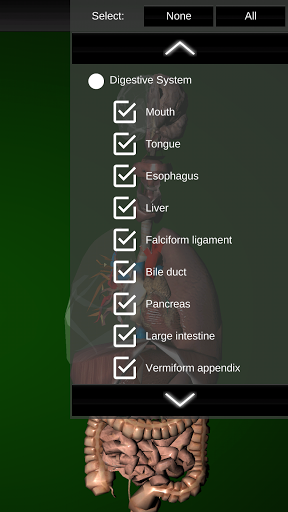

Internal Organs 3D Anatomy 3.4

Internal Organs 3D Anatomy 3.1

Organs 3D Anatomy 2.0.12